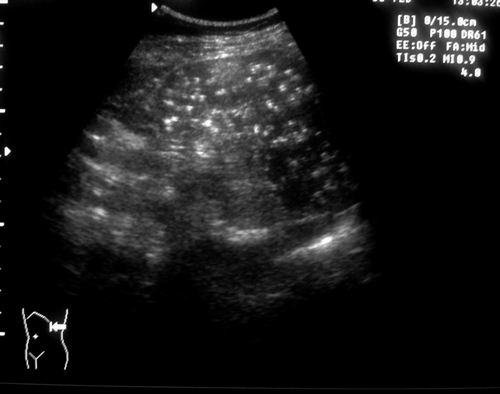

Кальцинаты селезенки "звездное небо"

В движении выглядит потрясающе, на самом деле как звездное небо

Чаще всего они единичные, а в данном случае "нет живого места"

ИМХО такие кальцинаты возникают после перенесённых инфекционных заболеваний, сопровождающихся гистиоцитарной инфильтрацией селезёнки (иерсиниоз, псевдотуберкулёз и др.). Очаги в этом случае как - правило множественные, обычно они есть ещё и в печени. То что мы видим - это отдалённое последствие и лечения не требует. Картинка конечно - же впечатляет.